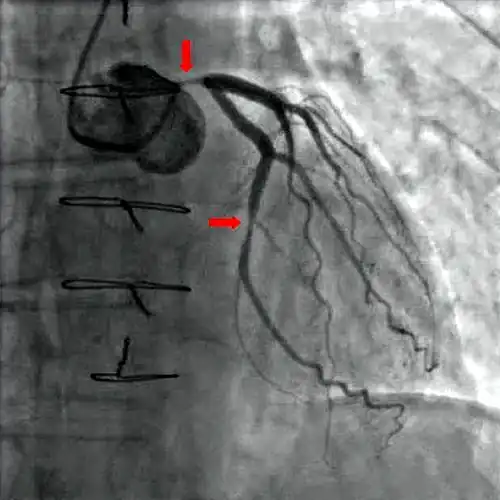

Koronarangiographie und Ventrikulographie

Mit Hilfe der diagnostischen Koronarangiographie können Koronararterien dargestellt und deren Anatomie sowie das Ausmaß und die Lokalisation eventueller Stenosen beurteilt werden. Sie ist die Untersuchung mit der besten Aussagekraft. Bei dieser Untersuchung wird ein Herzkatheter über die Arteria femoralis (Oberschenkelarterie) oder seltener über die Arteria brachialis (Oberarmarterie) bis zu den Abgängen der Koronararterien aus der Aorta vorgeschoben und Kontrastmittel in die Abgänge injiziert. Mit Hilfe von Röntgenstrahlung können die Koronararterien sichtbar gemacht und beurteilt werden.[24] Der Katheter kann, unter Überbrückung der Aortenklappe, weiter in die linke Herzkammer vorgeschoben werden. Diese Untersuchung wird als Ventrikulografie bezeichnet. Sie ermöglicht zusätzlich regionale Kontraktionsstörungen sichtbar zu machen, die zum Beispiel Hinweise auf zurückliegende Herzinfarkte bieten können, sowie eine Beurteilung der linksventrikulären Pumpfunktion über Berechnung der Auswurffraktion und die Bestimmung der Dehnbarkeit der Herzmuskulatur (Compliance) durch Bestimmung des enddiastolischen Volumens.[1]

Da es sich bei der Koronarangiographie und der Ventrikuloangiografie um invasive Untersuchungsmethoden handelt, kann es neben relativ ungefährlichen Komplikationen (beispielsweise Hämatome an der Einstichstelle) in sehr seltenen Fällen zu schwerwiegenden lebensbedrohlichen Komplikationen kommen. Dazu gehören vor allem Herzinfarkte, Schlaganfall, Spaltungen (Dissektionen) der Gefäßwände, Herzrupturen, Luftembolien und Arrhythmien.[4] Die Letalität der Untersuchung liegt unter 1:100.[1]

Aufgrund der nicht völlig ausschließbaren Risiken für das Auftreten von Komplikationen, der Strahlenbelastung sowie der Belastung der Nieren durch das Röntgenkontrastmittel, sollte die Indikation der Koronarangiographie zur Diagnose einer chronischen KHK relativ streng gestellt und im Sinne einer Nutzen-Risikoanalyse abgewogen werden. Nach den Empfehlungen der nationalen Versorgungsleitlinie (NVL) sollte diese Untersuchung nur dann erfolgen, wenn entweder alle nicht-invasiven Untersuchungsmethoden ohne Ergebnis ausgeschöpft wurden und trotzdem die Verdachtsdiagnose chronische KHK wahrscheinlich ist, oder wenn der Patient von Revaskularisationsmaßnahmen profitieren könnte.[4] Bei der Abwägung spielen des Weiteren bestehende kardiovaskuläre Risikofaktoren, zurückliegende Herzinfarkte und andere bestehende Herz-Kreislauf-Erkrankungen, die Einschätzung der Lebensqualität durch den Patienten sowie der Schweregrad der stabilen Angina pectoris nach CCS-Klassifikation eine wichtige Rolle. Für Letztere gilt, dass bei einem CCS-Stadium < III sowie bei erfolgreicher konservativer Pharmakotherapie, normalerweise keine Indikation für eine erneute Koronarangiografie besteht.[4]

Als diagnostische und therapeutische Maßnahme gilt die Darstellung der Herzkranzgefäße mittels Koronarangiographie als Goldstandard in der Diagnostik. In derselben Sitzung ist es möglich, signifikante Engstellen durch eine Ballondilatation (Perkutane transluminale coronare Angioplastie, PTCA), ggf. kombiniert mit der Implantation eines Stents aufzudehnen.